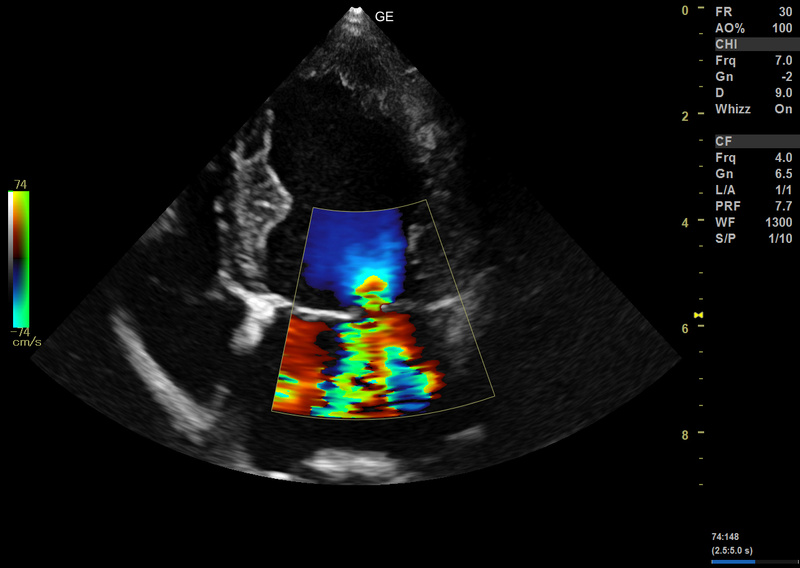

- B-Flow™ e Color B-Flow™

Tecnologia di imaging di elevata qualità

Versana Active™ è una soluzione completa che aiuta ad implementare le prestazioni veterinarie, bilanciando alla perfezione convenienza ed efficacia. Offre una potenza di imaging ai più alti standard mondiali ed estrema chiarezza per aumentare l'affidabilità diagnostica.

Le migliori tecnologie sviluppate da GE in tutti gli ambiti specialistici come cardiologia, muscolo scheletrico, ecografia vascolare sono ora disponibili in un’unica piattaforma: Versana Active™. Scegli la tua versione!